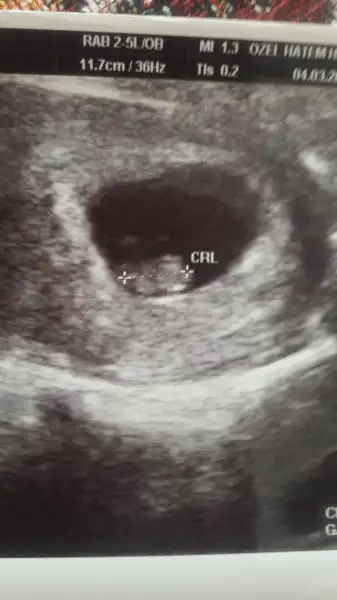

Kızlar cinsiyet tahmini yapar misiniz gerçi daha 7 haftalık :)

Karından ise usg erkek diyorum :) doğru çıkarsa haber ver lütfen :)Kızlar cinsiyet tahmini yapar misiniz gerçi daha 7 haftalık :)

banada erkek gibi geldi oglusumun durusu gibi duruyo:)Kızlar cinsiyet tahmini yapar misiniz gerçi daha 7 haftalık :)

Hadi bakalım bu dahaki kontrolde çıkar cnm genelde bana erkek dediler yani kiz diyen az benim.içinden kiz geciyo eşimin erkek geciyo bakalım hayırlısı ile kuacahimiza alırız inslahhh kizlarbanada erkek gibi geldi oglusumun durusu gibi duruyo:)

Evet cnm karından tamam cnm 1 ay sonra haber veririm gösterirse bebis kendiniKarından ise usg erkek diyorum :) doğru çıkarsa haber ver lütfen :)